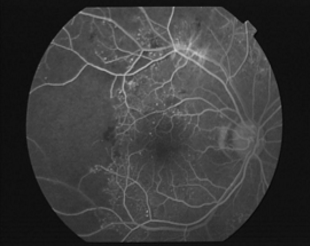

视神经病变